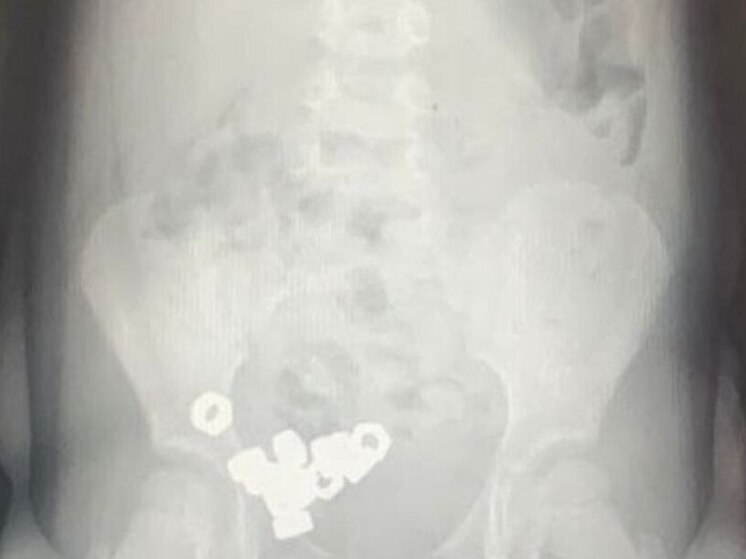

В Воронеже трехлетний ребенок проглотил 16 гаек. Малыша оперативно доставили в областную детскую больницу №2, где ему оказали необходимую помощь. Информацию об инциденте предоставил региональный Минздрав.

Как сообщили родители юного пациента, он мог проглотить посторонние предметы. На момент врачебного осмотра симптомы отсутствовали, но рентген подтвердил наличие небольших гаек в желудочно-кишечном тракте ребенка.

Малыша госпитализировали для наблюдения и лечения. Врачи выбрали консервативный подход, поскольку гайки не были магнетическими или инертными. Лечение включало специальную диету, покой, регулярный мониторинг стула и динамическую рентгенографию.

На третий день все гайки вышли естественным путем, после чего ребенка выписали из больницы.